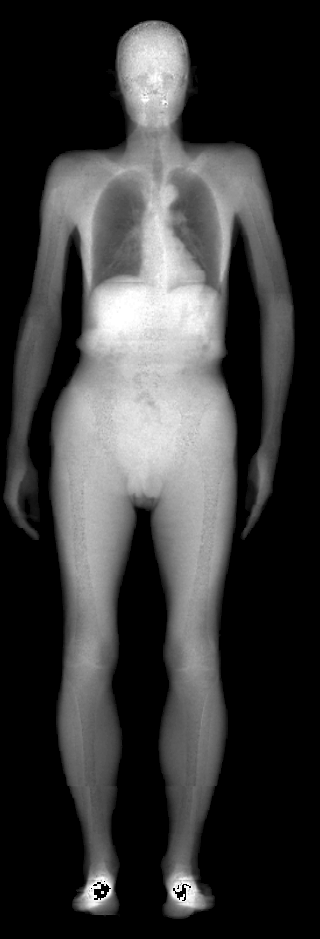

The key problem, however, is obtaining training data that simultaneously gives the inside and outside of the body in 3D. Most imaging technologies that simultaneously capture the inside and outside of the body use ionizing radiation, which is harmful to humans; e.g. Computed Tomography (CT) and X-rays. This means that such data is extremely limited, preventing learning-based methods. Our insight is to use dual-energy X-ray absorptiometry (DXA) data. DXA scans use low-dose X-rays to measure bone mineral density and body fat composition. The radiation level is so low that it is certified to be used on healthy patients for clinical studies, such as the UK Biobank [36]. In a DXA scan, two images are computed by combining two different energy levels: a soft-tissue image and a bone image (Fig. 2). In the silhouette of the body can clearly be seen, whereas reveals the structure and shape of the bones.

From the input images (, ), we compute the corresponding skin and skeleton segmentation masks (, ). For the skin mask , we threshold . As some small artifacts remain, mainly due to pixels in the lungs with low intensity values, we detect the closed contours on the image and fill in small areas. In Fig. 2 we show pairs of input and the obtained mask .